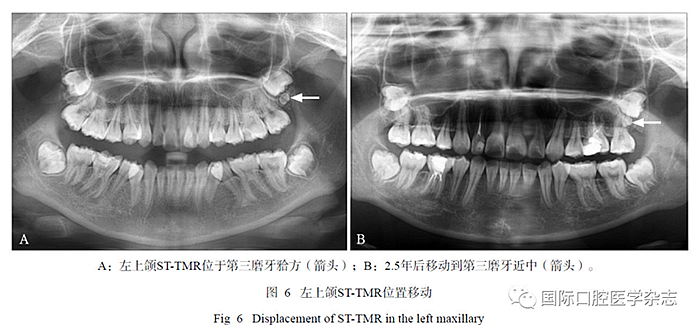

在17例有隨訪拍片的患者中,2例新增STTMR,其中1例患者第一、第二次拍片年齡分別為10歲、13歲(間隔2年7個月),另1例患者第一次、第二次拍片年齡分別為9歲、11歲(間隔2年,圖5);1例發(fā)生位置改變,ST-TMR由上頜第三磨牙方向近中移動(間隔2.5年,圖6)。

ST-TMR在生長發(fā)育中可發(fā)生位置移動,1例患者前后間隔2.5年的曲面體層片對比,發(fā)現(xiàn)左上頜ST-TMR在發(fā)育中由第三磨牙方向近中移動,這種現(xiàn)象符合恒牙生長萌出過程中向近中移動的一般規(guī)律,同時牙弓缺乏空間或擁擠也可導致牙胚旋轉(zhuǎn)移動,這也是造成ST-TMR或第三磨牙阻生、異位最常見原因之一[15]。